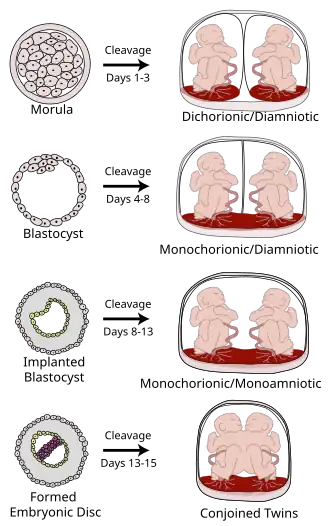

Monochorionic twins are monozygotic (identical) twins that share the same placenta. If the placenta is shared by more than two twins (see multiple birth), these are monochorionic multiples. Monochorionic twins occur in 0.3% of all pregnancies.[1] Seventy-five percent of monozygotic twin pregnancies are monochorionic; the remaining 25% are dichorionic diamniotic.[2] If the placenta divides, this takes place before the third day after fertilization.[2]

Monochorionic twins generally have two amniotic sacs (called Monochorionic-Diamniotic "MoDi"), but sometimes, in the case of monoamniotic twins (Monochorionic-Monoamniotic "MoMo"), they also share the same amniotic sac. Monoamniotic twins occur when the split takes place after the ninth day after fertilization.[2] Monoamniotic twins are always monozygotic (identical twins).[3] Monochorionic-Diamniotic twins are always monozygotic.